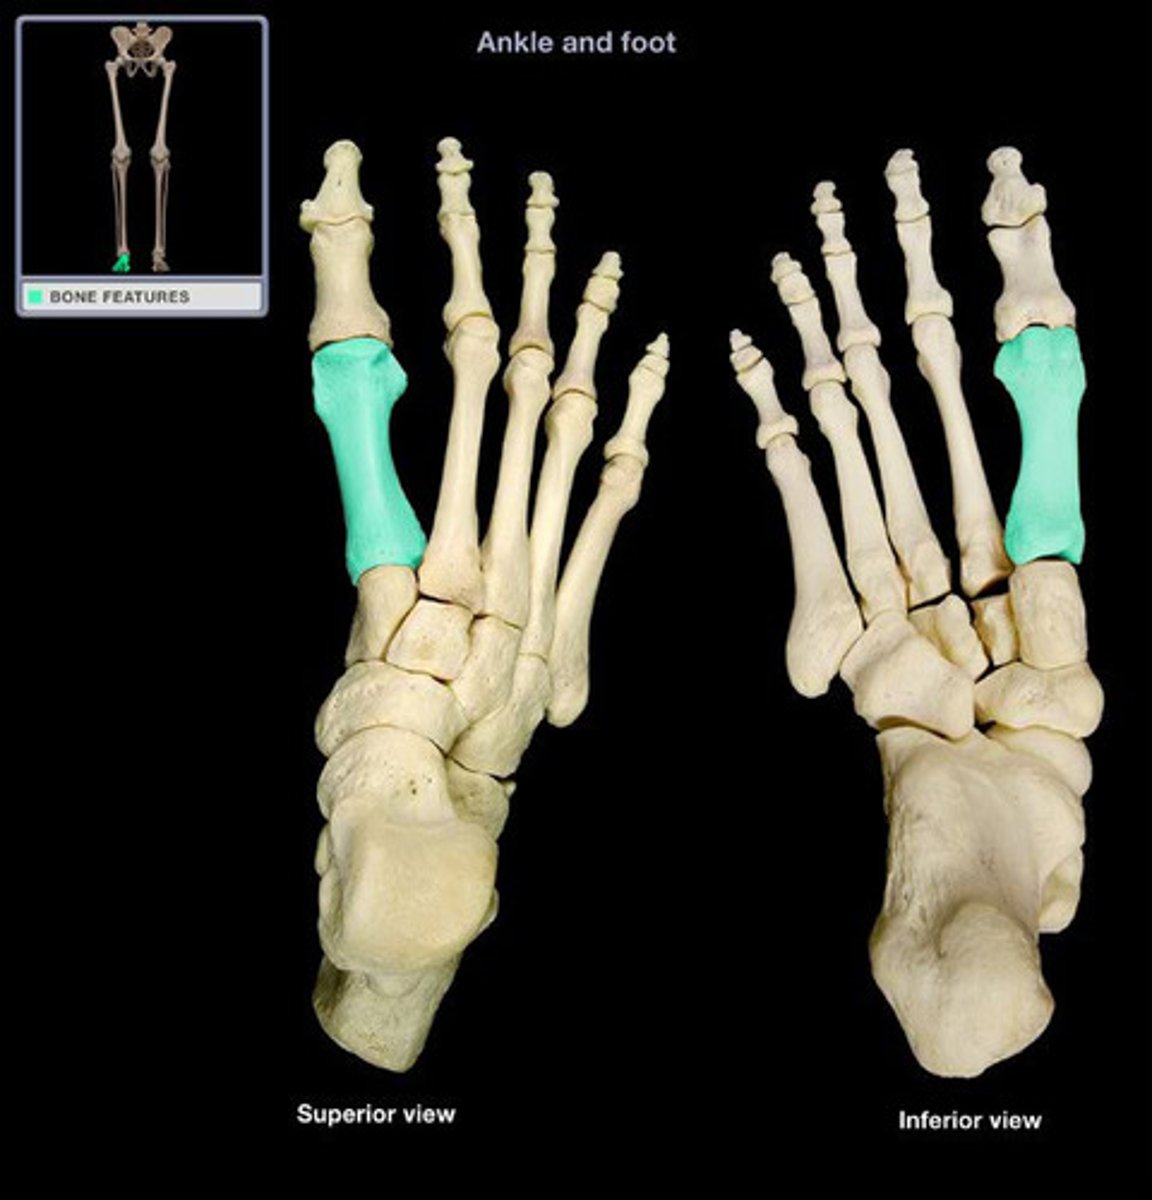

First metatarsal